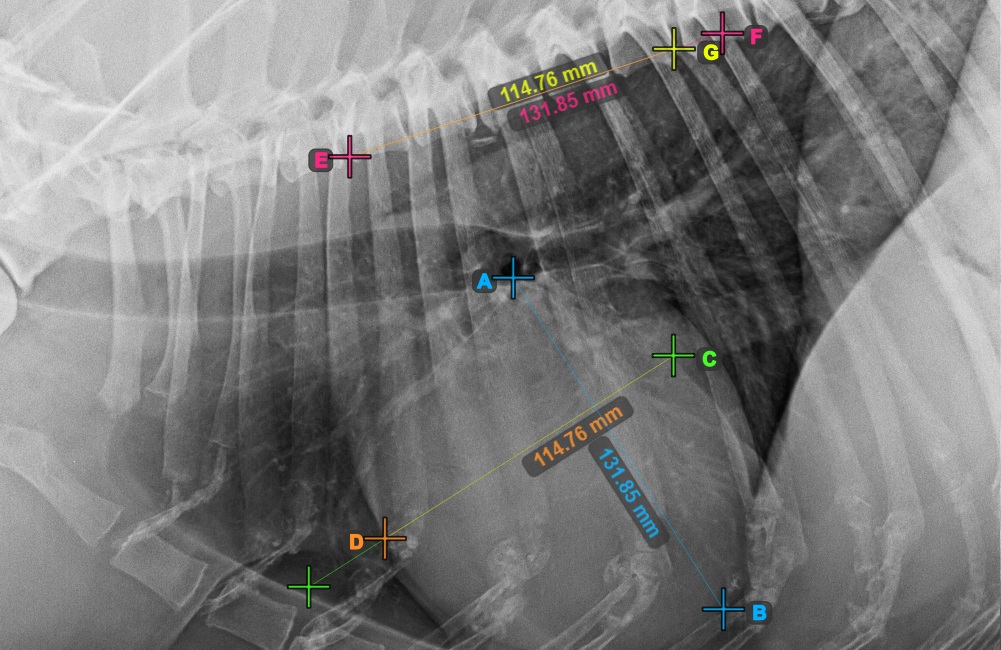

Identify the beginning of the T4 vertebra (the fourth vertebral body of the spine), counting from the initial point of the spine. Mark the beginning of the T4 vertebrae to continue the measurement. The software will draw lines from the marked point along the spine. The length of the lines depends on the measured long and short axes of the heart.

The image below represents the typical placement of the point at the beginning of the fourth vertebral body of the spine.

Before proceeding with the required VHS calculations, make sure that the lines are placed precisely along the vertebrae.

Count the number of vertebrae along the line representing the short axis on the spine. Specify the required vertebrae count in the Vertebrae Count

input field in the advanced measurement mode toolbar.